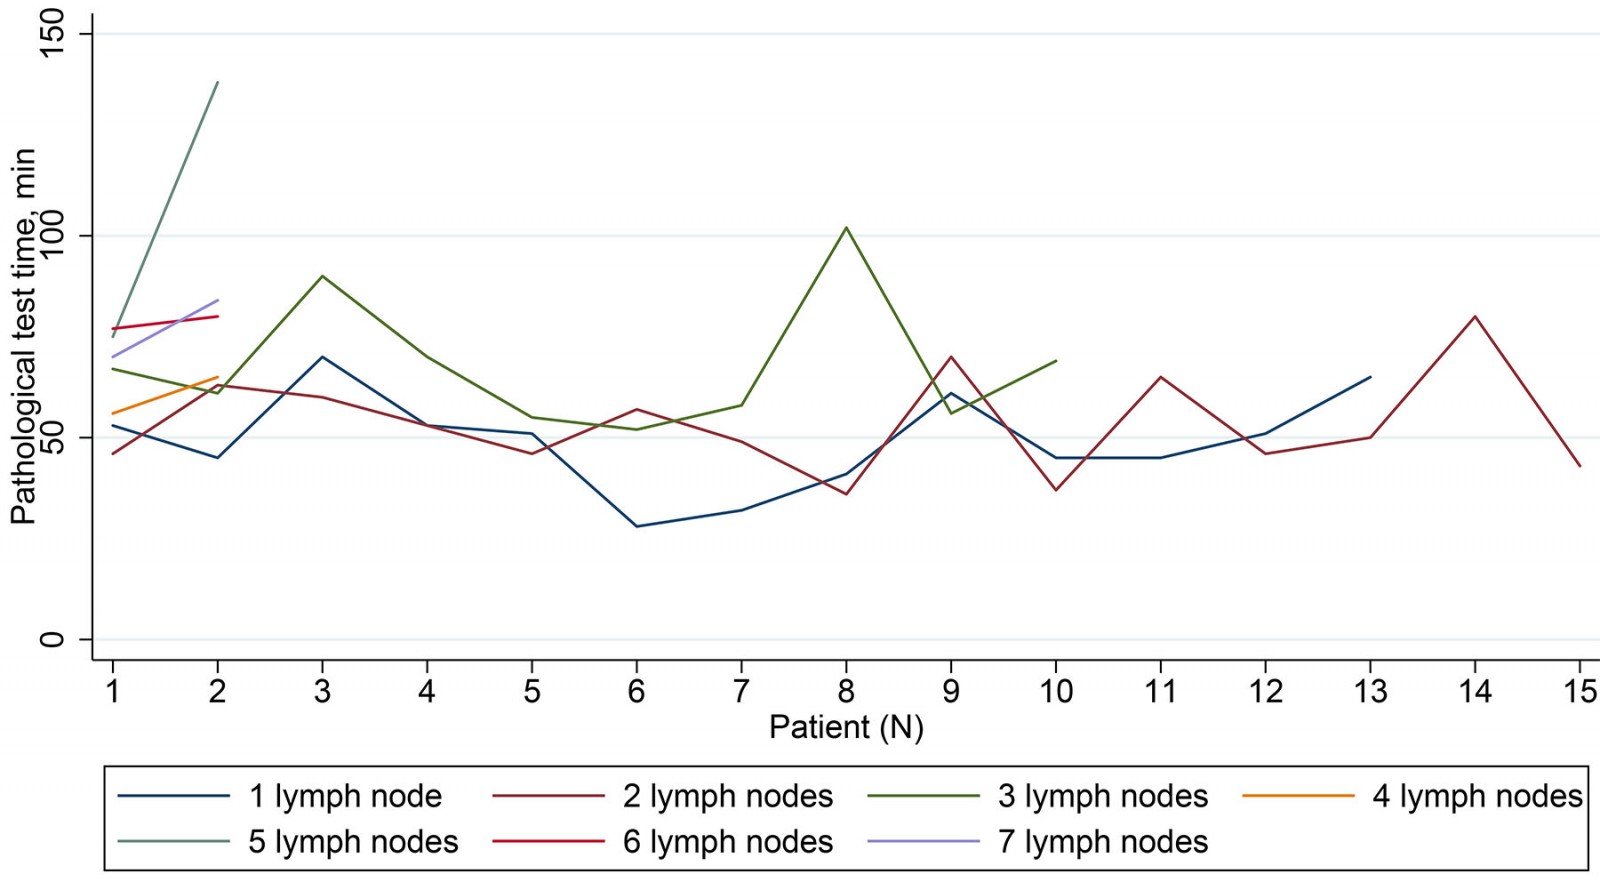

The average examination time required for a remote diagnosis of sentinel lymph node was 61 minutes (69 minutes by the cloud-based medical record system and 54 minutes by the simultaneous videoconferencing system). There was no apparent difference in the time required for remote consultation as stratified by the number of examined lymph nodes (Fig2).

Figure 2: Time required for remote consultation as stratified by number of examined lymph nodes.

Figure 2: Time required for remote consultation as stratified by number of examined lymph nodes.